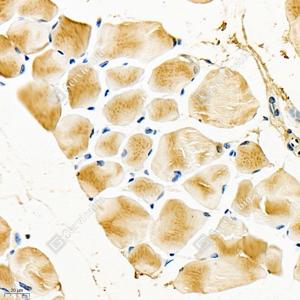

IHC检测Igfn1蛋白(货号 GB112397). 样品: 小鼠骨骼肌, 4%多聚甲醛 (货号G1101) 固定12-24小时. 抗原修复: Tris-EDTA抗原修复液(pH 9.0) (G1203), 98℃, 20分钟. —抗: 1: 700稀释, 4℃ 孵育过夜. 二抗: HRP标记山羊抗兔IgG (H+L) (货号GB23303), 1: 200稀释, 室温孵育1小时. |